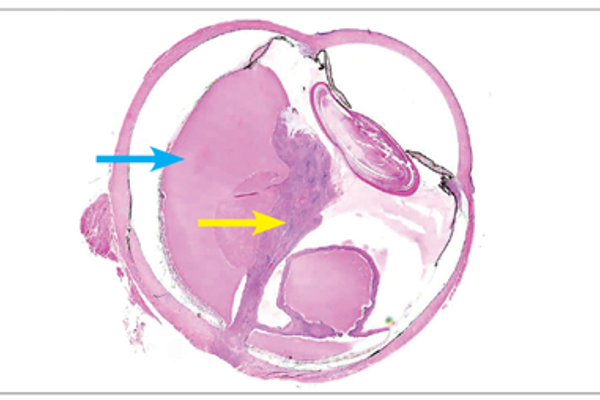

Pathology Quiz - Section Editor until Aug/Sep 2016